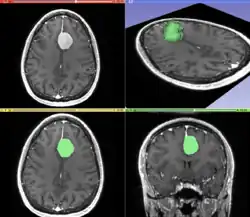

Information can take the form of images, sound, video or other multimedia. Bits of information can be streamed via signals. Its processing is the central notion of informatics, the European view on computing, which studies information processing algorithms independently of the type of information carrier – whether it is electrical, mechanical or biological. This field plays important role in information theory, telecommunications, information engineering and has applications in medical image computing and speech synthesis, among others. What is the lower bound on the complexity of fast Fourier transform algorithms? is one of the unsolved problems in theoretical computer science.

FFT algorithms Image processing Speech recognition Data compression Medical image computing Speech synthesis